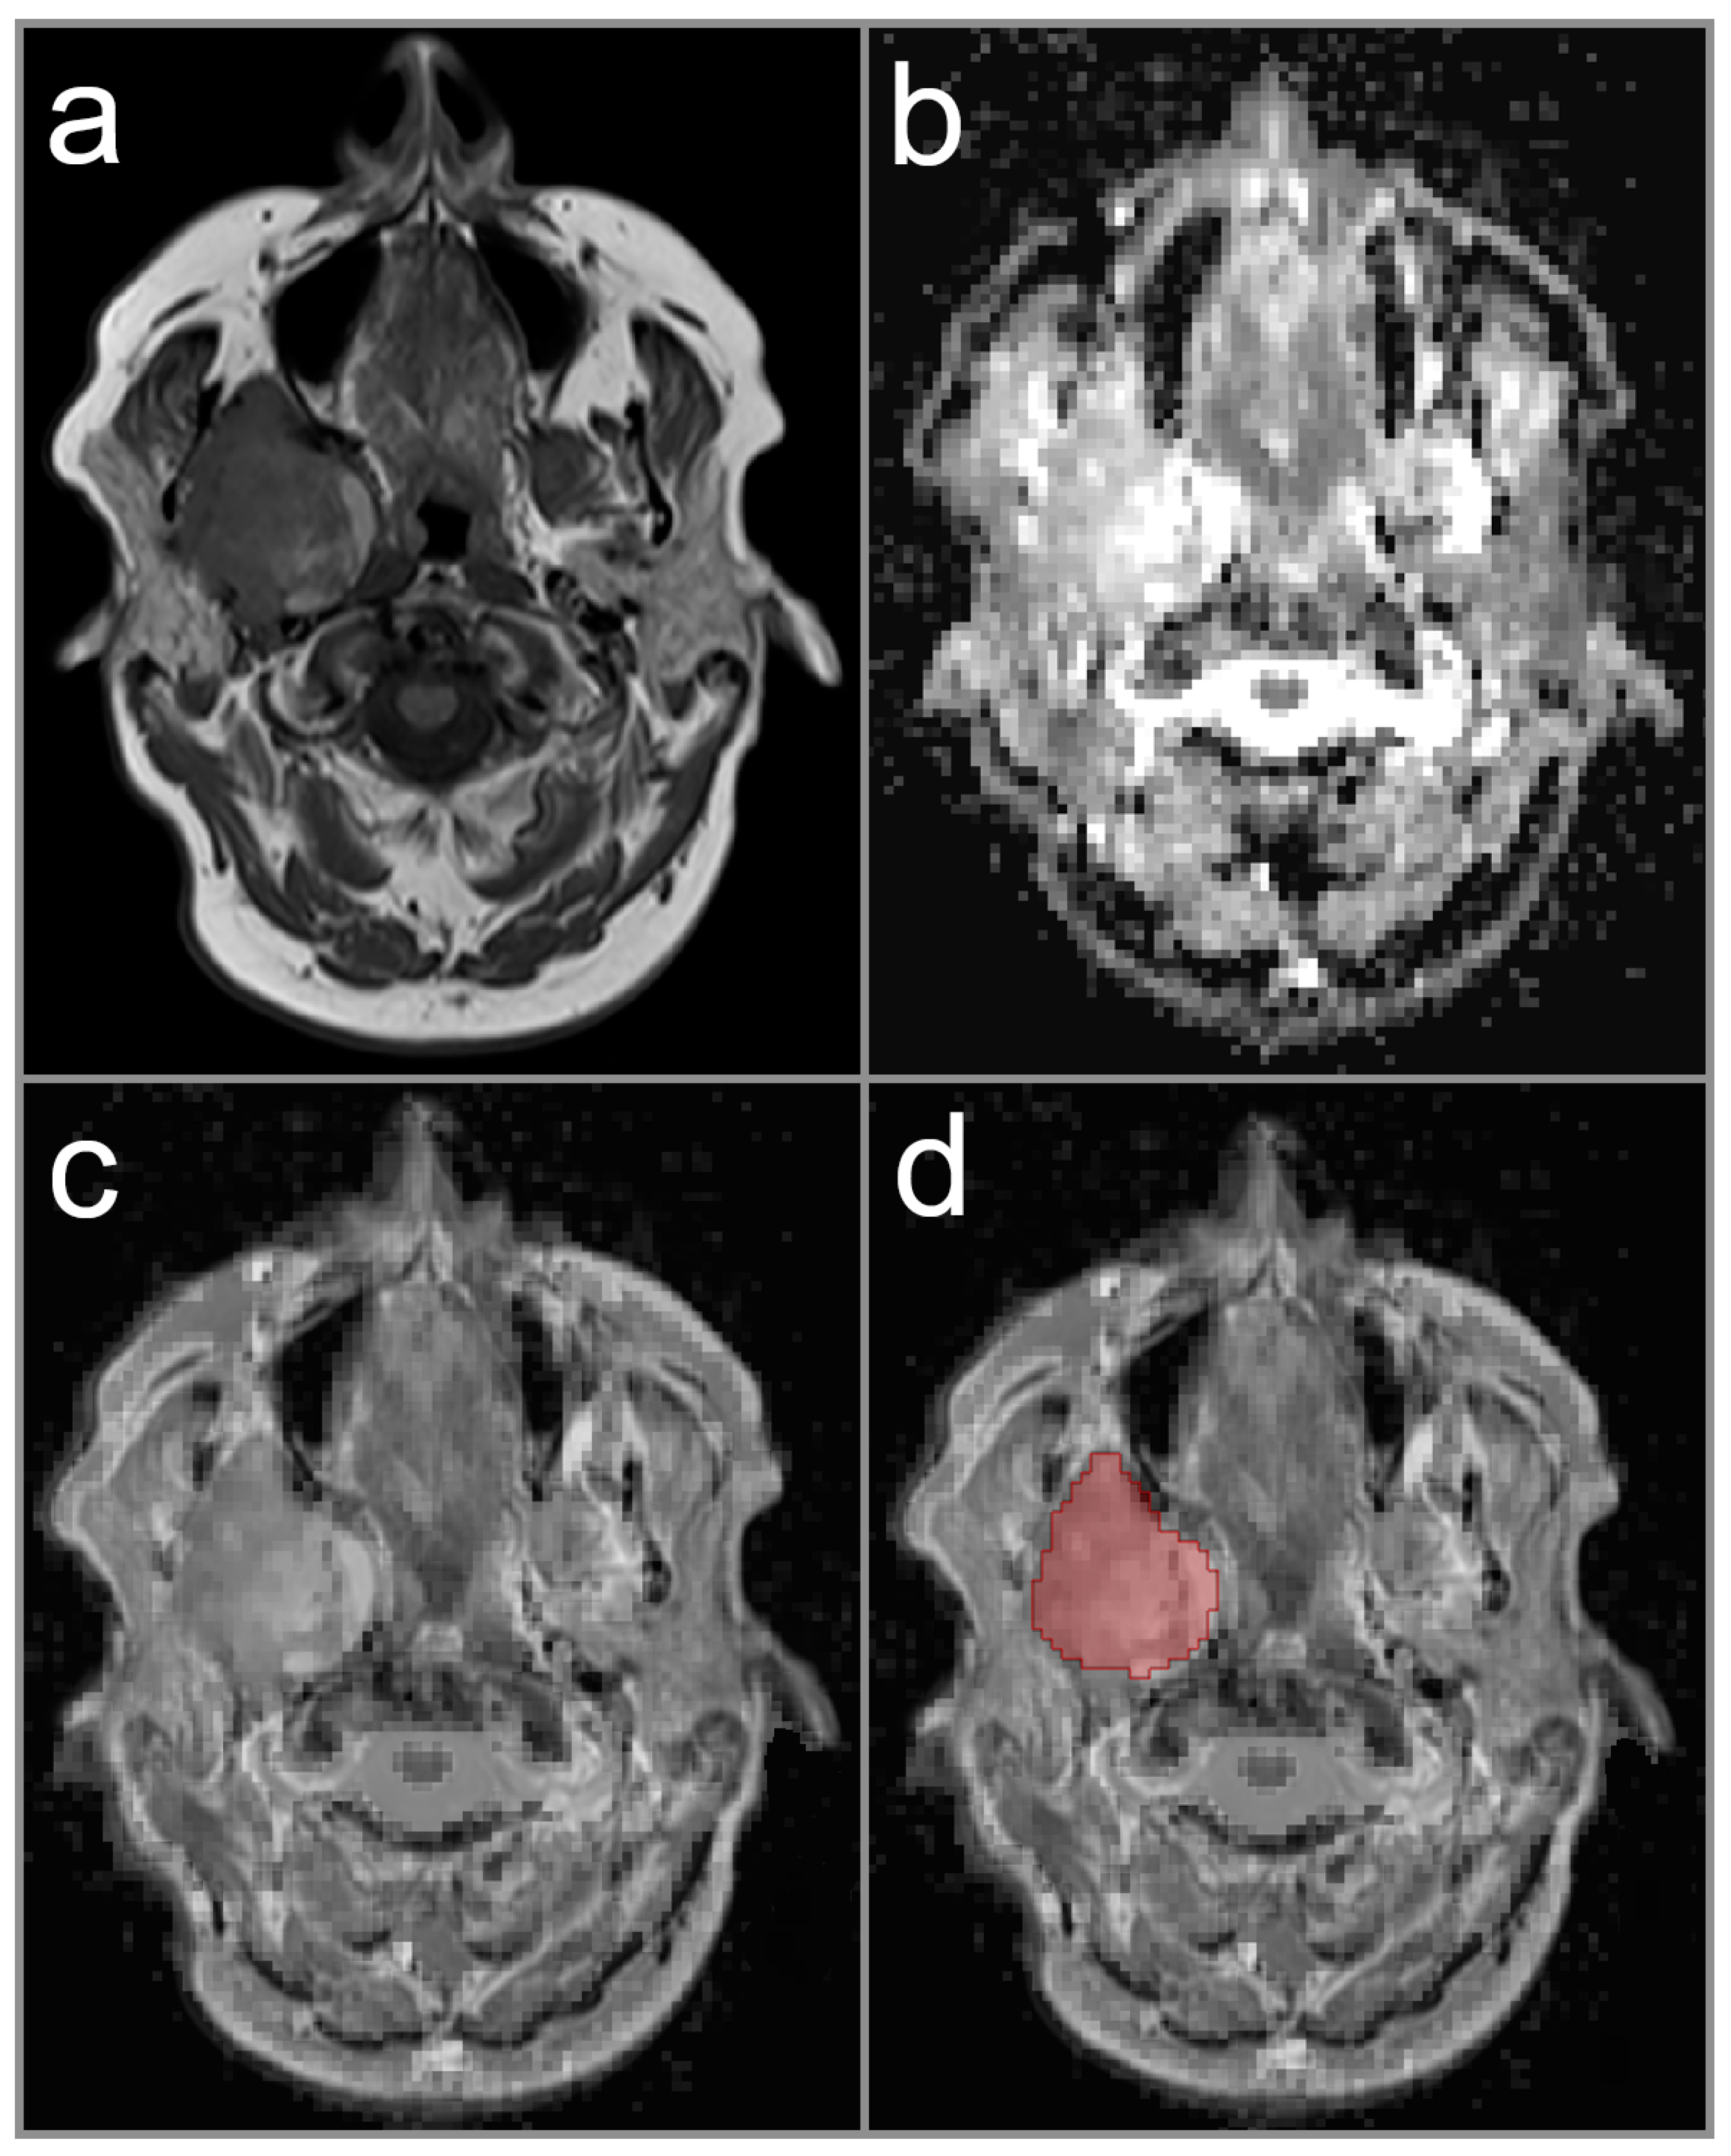

2.3. Image Analysis and ADC Measurement